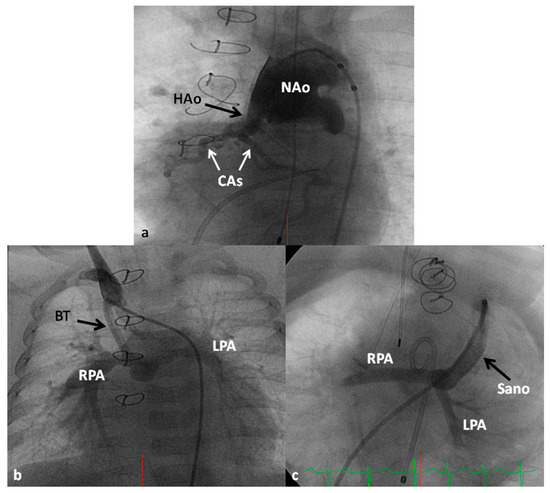

In the Norwood procedure [97,98,99], the PA and the Ao are anastomosed with the use of additional prosthetic material as needed, atrial septectomy is performed to ensure unrestricted blood flow across the atrial septum, the ductus arteriosus is ligated, coarctation of the aorta, if any, is eliminated and an aorta-to-pulmonary artery shunt (usually a modified BT shunt) is created to supply pulmonary blood flow (Figure 13). Thus, the systemic circulation is supported by the RV and the pulmonary circulation is provided by the modified BT shunt. The Norwood procedure is usually performed around the age of one week, after stabilization of the infant as detailed above.

Some of the poor results following Norwood have been attributed to lower diastolic coronary perfusion pressures and to address this problem, Sano and his associates [105,106] replaced modified BT shunt with a RV outflow tract to PA Gore-Tex graft (Figure 13C); this procedure is now called the Sano modification of Norwood. Comparison of these two procedures among contemporary patient groups did not discover any advantage of one technique over the other [107,108]; however, most centers seem to favor the Sano modification of Norwood.